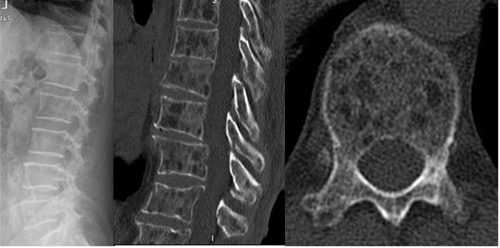

Fig 193. Mieloma.

A: Rx lateral, B: TAC reconstrucción sagital y C: TAC axial en ventana osea.

Moderada osteoporosis, con lesiones líticas que comprometen todas las vértebras.